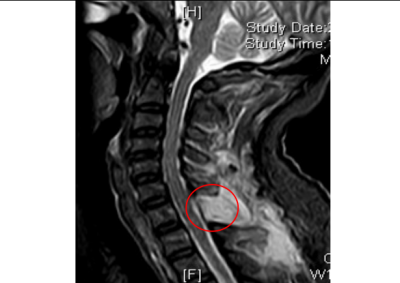

术后复查核磁检查,颈胸段椎管内肿瘤已切除干净

若不尽快手术切除肿瘤,随着肿瘤持续增大,脊髓受压程度会不断加重,进而造成不可逆的神经损伤,最终甚至可能导致四肢瘫痪。接下来,脊柱外科一区主任、主任医师许宇霞带领团队成功为张淮实施了高难度颈胸段椎管内肿瘤切除术。术中快速病检提示肿块为“神经鞘瘤”,这类肿瘤多为良性肿瘤,手术切除后预后良好,复发率低。术后张淮恢复良好,原有颈肩疼痛消失,左上肢麻木无力及右下肢行走无力等症状均显著改善。